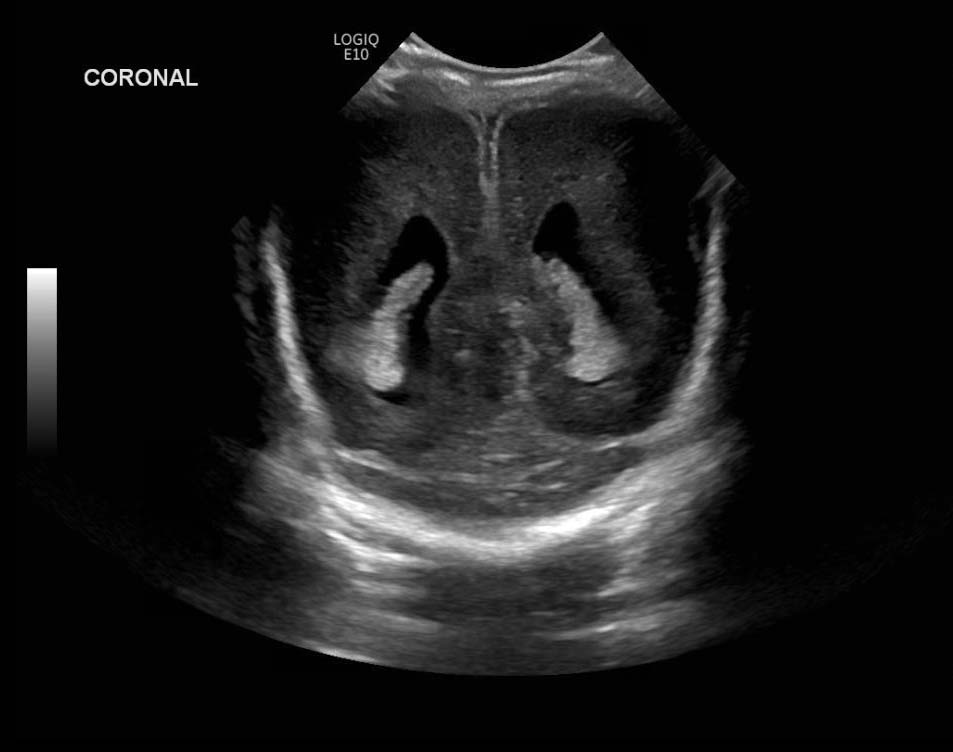

Age: 4 days (born at 24 weeks)

Sex: Male

Indication: Evaluate for germinal matrix hemorrhage

Grade 2 germinal matrix hemorrhage

Sample ReportLeft germinal matrix hemorrhage involving the caudothalamic groove and layering in the occipital horn of the left lateral ventricle without hydrocephalus (grade 2).

No abnormal brain parenchymal echogenicity or extra-axial collections.

Premature sulcation pattern.